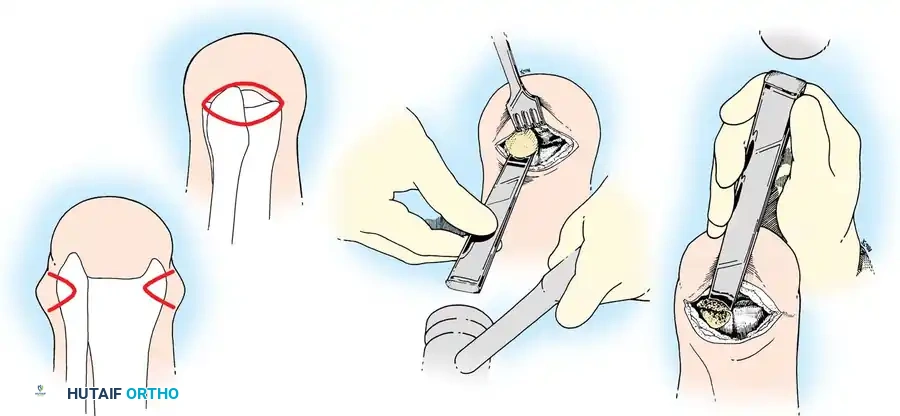

Step 1: Incision and Exposure

- Place the patient supine. A single, long posterior heel flap is utilized.

- Begin the incision at the distal tip of the lateral malleolus. Pass it across the anterior aspect of the ankle joint at the level of the distal tibia to a point exactly one fingerbreadth inferior to the tip of the medial malleolus.

- Extend the incision directly plantarward, across the sole of the foot to the lateral aspect, ending at the starting point.

Step 2: Joint Disarticulation

- Divide all anterior structures straight down to the bone. Ligate the anterior tibial artery as it lies in the anterior flap.

- Place the foot in marked equinus and divide the anterior capsule of the ankle joint to expose the talar dome.

- Insert a scalpel into the joint space between the medial malleolus and the talus. Draw it inferiorly to section the deltoid ligament. Crucial: Protect the posterior tibial artery lying immediately posterior to the medial malleolus.

- Repeat this maneuver on the lateral side to section the calcaneofibular ligament.

Step 3: Posterior Dissection and Calcanectomy

- Place a bone hook into the posterior aspect of the talus to provide forceful equinus traction. Proceed with posterior dissection, dividing the posterior capsule of the ankle joint.

- Identify the Achilles tendon. Divide it directly at its insertion on the calcaneus.

Pitfall: Do not damage the overlying posterior skin during Achilles tenotomy. Buttonholing the skin here will lead to necrosis of the entire heel flap.

- Using a periosteal elevator, dissect the soft tissues from the lateral and medial surfaces of the calcaneus. Pull the bone into extreme equinus.

- Continue subperiosteal dissection on the inferior surface of the calcaneus until the distal end of the plantar skin flap is reached. Remove the entire foot, leaving only the heel flap.

Step 4: Bone Transection

- Retract the heel flap posteriorly. Dissect the soft tissue from the tibia and malleoli.

- Incise the periosteum circumferentially 0.6 cm proximal to the joint line.

- Using an oscillating saw, divide the tibia and fibula at this level. The line of transection must pass just through the dome of the ankle joint centrally.

- Alignment: The plane of the transection must be perfectly parallel to the ground when the patient is standing. Round and smooth all sharp cortical edges with a rasp.

Step 5: Soft Tissue and Nerve Management

- Identify the medial and lateral plantar nerves. Dissect them proximally and divide them sharply under tension so they retract well proximal to the bone end, preventing symptomatic neuroma formation.

- Pull all visible tendons inferiorly, section them, and allow them to retract proximally into the leg.

- Isolate the posterior tibial artery and vein. Ligate them just proximal to the cut distal edge of the heel flap.

- Perform minimal debridement of any soft-tissue tags of plantar muscle and fascia lining the inner surface of the heel flap.

Clinical Pearl: Preserve the subcutaneous fat and its fibrous septa entirely intact. This is highly specialized, pressure-tolerant tissue designed for weight-bearing. Stripping this fat destroys the hydraulic shock-absorbing capacity of the heel.

Step 6: Anchoring the Heel Pad (Wagner Technique)

To prevent the disastrous complication of posterior heel pad migration, the pad must be rigidly fixed to the distal tibia.

* Drill several small holes through the anterior edge of the distal tibia and fibula.

- Pass heavy, nonabsorbable sutures through these drill holes and anchor them securely to the robust deep fascia lining the heel flap.

Step 7: Closure

- Approximate the skin edge of the heel flap to the anterior flap using interrupted nonabsorbable sutures. Ensure there is absolutely zero tension on the closure.

- Crucial Step: Large, protruding tags of skin ("dog ears") will form at the medial and lateral ends of the suture line. Never excise these. They carry the primary blood supply to the heel flap and will naturally remodel and shrink under postoperative bandaging.